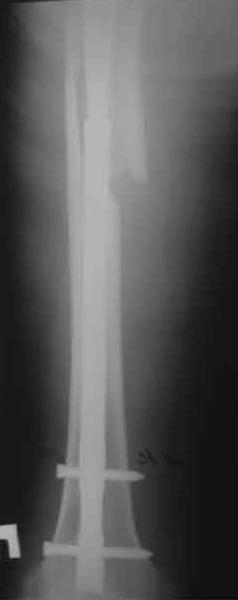

Произведено закрытое удлинение ножки эндопротеза с помощью ретроградного интрамедуллярного стержня. Продолжительность операции 3 часа. Два из них закрытое восстановление длины бедра диистрактором

таз-бедро.

А нельзя ли увидеть и профиль бедра на всем протяжении, т.е. и весь протез, и весь стержень? И фас бы с коленом.

новые снимки

Пациента удалось осмотреть недавно. Достигнутый результат сохраняется. Перелом бедра сросся. Конечность опорная и безболезненная, ходит без трости. Ножка, похоже, реинтегрировалась, как и надеялись. Снимки и фото в приложении. Комментарии приветствуются.

Надо ли что-то делать дальше, как полагаете? Убрать винты? Убрать "удлинитель ножки"? Или оставить все, как есть? Спасибо заранее.